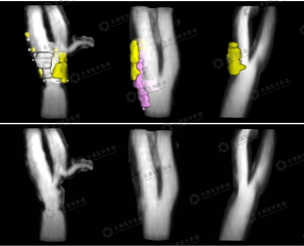

病史:患者男性,59岁,主要临床症状,偶有头晕,健康体检,斑块筛查。通过VPD检查出易损斑块。及时干预,避免了脑卒中的发生。VPD报告显示:右侧颈内动脉起始部后壁可见斑块形成,其内成分复杂,斑块内成份为脂质坏死核及疏松基质,并见出血,局部溃疡形成,其中出血占比小于20%,脂质坏死核最大面积小于20%。符合AHA type VI型斑块,易损斑块;右侧颈内动脉管腔呈中度狭窄伴易损板块形成(斑块出血、溃疡形成)。

病史:患者男性58岁,最近有脑卒中病史,行颈部斑块检查。通过VPD检查出大量易损斑块。VPD检查报告显示:左侧颈总动脉、分叉处、颈内动脉均可见斑块形成,其内成分复杂,斑块内成份为脂质坏死核、钙化及疏松基质,并见大面积出血,其中出血占比大于50%,脂质坏死核最大面积为20-40%。符合AHA type VI型斑块,易损斑块;左侧颈内动脉管腔呈重度狭窄。